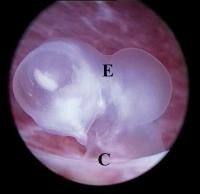

GD2-Embryo

Abbildung 4: GD2-Embryo mit einer SSL von 3 mm. Eine Unterscheidung von kranialem und kaudalem Embryonalpol ist nicht möglich. Der Embryo (E) ist direkt an der Chorionplatte (C) adhaerent. Ein offenbar normaler Karyotyp (46,XY) wurde zytogenetisch diagnostiziert.